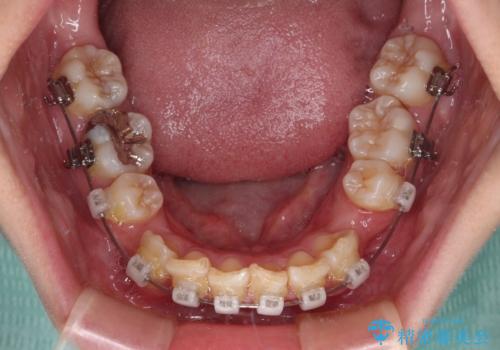

- クリアブラケット

- 2年9ヶ月

- 10-30回